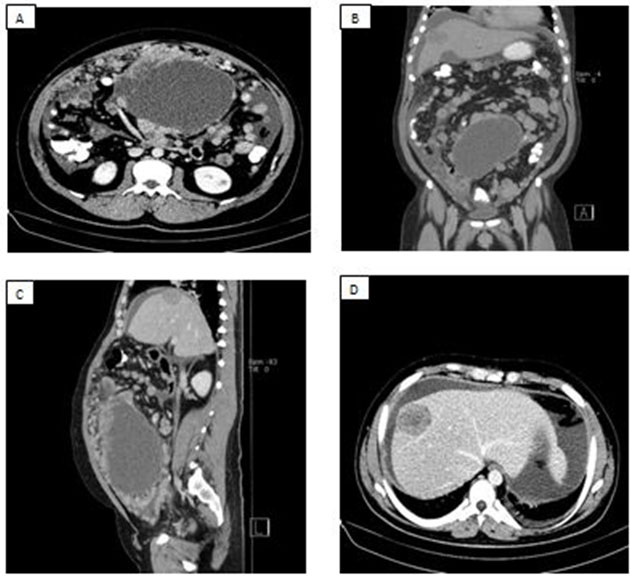

A 22-year-old male with very severe aplastic anemia who failed immunosuppressive therapy and was considered for therapeutic bone marrow transplant. He was without human leukocyte antigens (HLA)-matched potential donors and ultimately underwent umbilical cord stem cell transplantation following conditioning with fludarabine, cyclophosphamide, thiotepa, and total body irradiation. His course was complicated by steroid-refractory gut GVHD treated with tacrolimus, prednisone, and ruxolitinib. During treatment for GVHD he developed progressive renal dysfunction and refractory hypertension; symptoms not commonly associated with GVHD. His renal function declined precipitously prompting a renal biopsy that demonstrated findings suggestive of acute and chronic thrombotic microangiopathy (TMA), as demonstrated in Figure 1. Tacrolimus was discontinued and alternative immunosuppression was initiated. Approximately eight weeks from his original diagnosis of TMA, his course was further complicated by hypoxic respiratory failure in the setting of cryptogenic organizing pneumonia and was suspected to be pulmonary GVHD, requiring renewal of immunosuppression with increasing doses of prednisone.

Figure 1: (A) The glomerular capillary lumina appear focally narrowed by accumulation of pale fluffy material (periodic acid–Schiff stain; original magnification, ×400). The glomerular capillary loops reveal several double contours of the basement membranes. (B) Ultrastructural examination reveals that the subendothelial space of the basement membrane is diffusely expanded by electron-lucent fluffy material (original magnification, ×3000). Entrapped fragmented erythrocytes (→) are noted in the subendothelium.